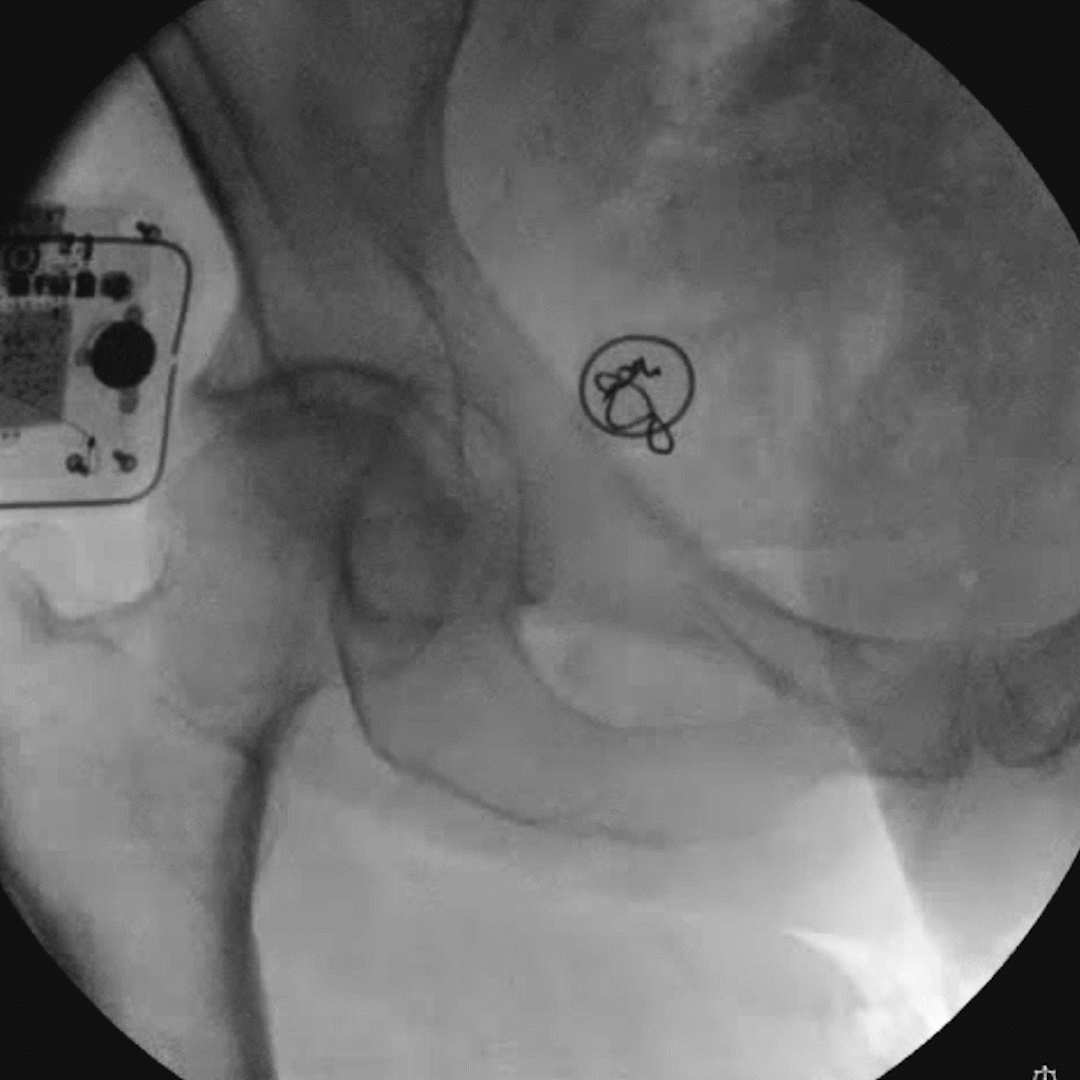

Neuromodulation devices targeting the dorsal root ganglion and nerves as well as nerve rootlets connecting into the DRG have technically challenging and time-consuming placement procedures. The Injectrode’s innovative placement procedure, with only 5 steps, has simplified how leads near the DRG can be placed. Relying on a transforaminal approach, similar to steroid injection pathways, present a development of a promising, minimally invasive alternative to the current standard of care.

The ‘scotty-dog’ landmark allows for repeatable injection of the device stimulator on the dorsal aspect of the roots as they exit the foramen. The delivery needle may be positioned between the likely location of the DRG and the pedicle at an oblique angle, then advanced off the bone to enter the dorsal aspect of the foramen. In this placement approach, the epidural space is not entered, and the Injectrode’s position relative to the ganglion enables stimulation.

Large animal and cadaver studies are underway to further characterize this placement approach.